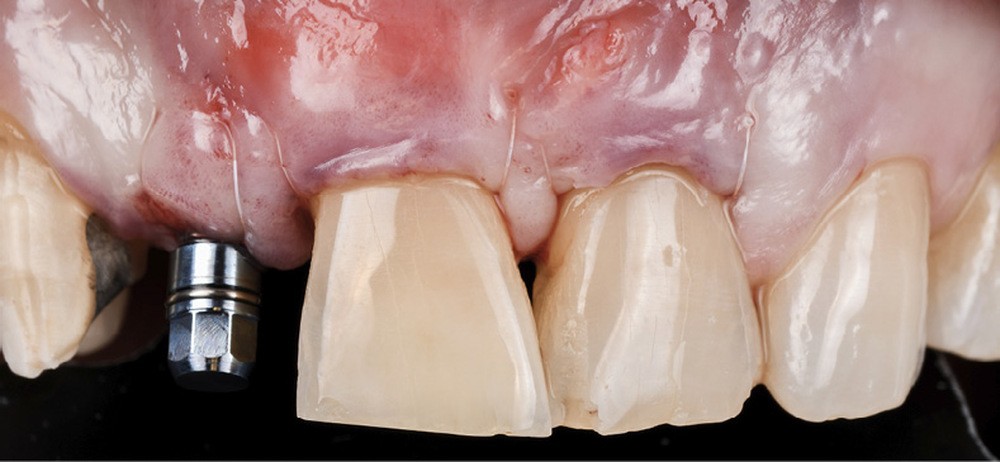

Il est établi que certaines règles de positionnement implantaire doivent être respectées en secteur antérieur afin de prévenir la survenue de déhiscence tissulaire. L’implant doit respecter une distance minimale de 1,5 mm avec les dents adjacentes, se trouver 2 mm en retrait de la ligne joignant les bords libres de ces dernières et présenter un col implantaire enfoui d’au moins 3 mm par rapport à la future position du collet prothétique.

Un rapport de consensus publié en 2022 [1] a formulé des conclusions concernant les facteurs susceptibles d’influencer les déhiscences de tissus mous péri-implantaires. Parmi les facteurs de risque identifiés, nous pouvons citer une angulation trop vestibulaire lors du positionnement implantaire et un phénotype péri-implantaire fin.

Ce tissu conjonctif peut être prélevé soit au palais, soit à la tubérosité. Comme le montre…